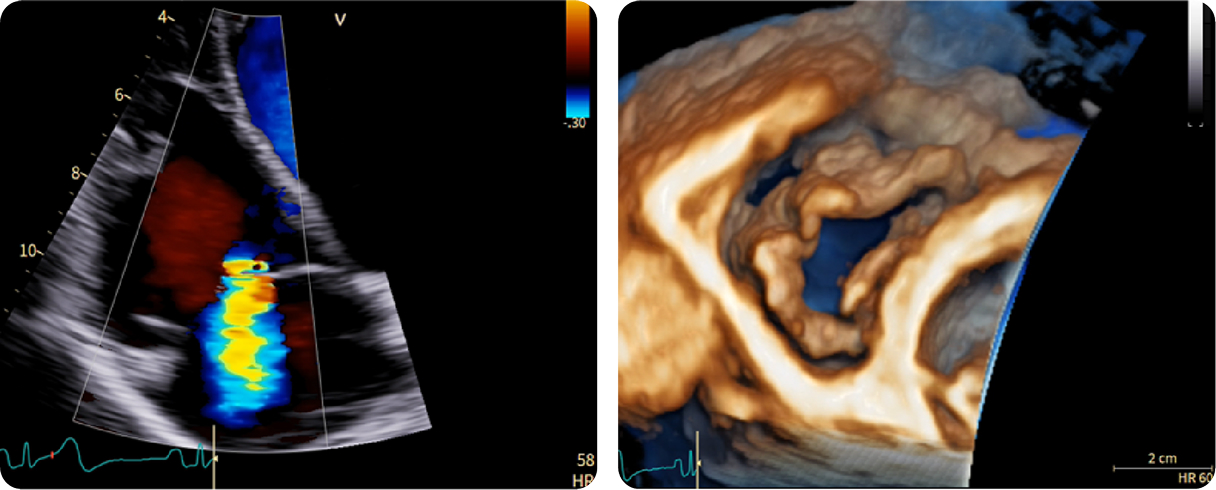

Fifty shades of grey

Caso condiviso da Marcello De Santis